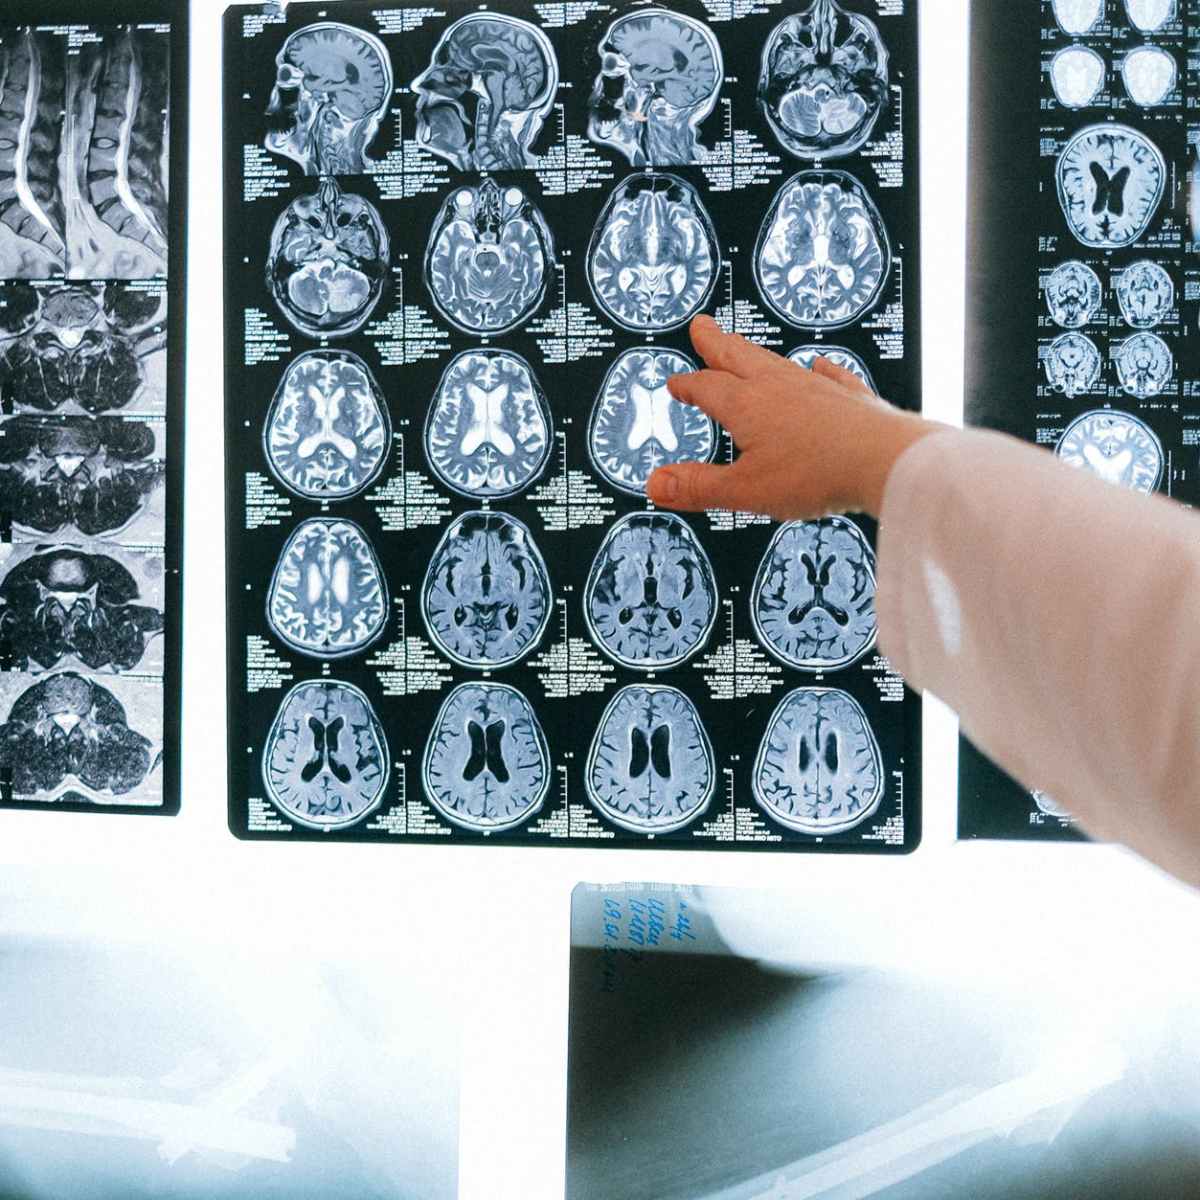

Dalla ricerca alla pratica clinica Nella malattia di Alzheimer il precoce accumulo di peptide beta-amiloide, insieme alla formazione e precipitazione della proteina tau iperfosforilata in grovigli neurofibrillari, rappresenta la firma patognomonica del processo neurodegenerativo e ne costituisce il nucleo biologico caratteristico. Pur non essendo l’unico determinante della cascata patogenetica, l’amiloide svolge certamente un ruolo essenziale…

I biomarcatori plasmatici nella malattia di Alzheimer

I biomarcatori plasmatici stanno emergendo come strumenti promettenti per la diagnosi precoce e il monitoraggio della malattia di Alzheimer, offrendo un approccio meno invasivo rispetto alle tecniche tradizionali. Secondo recenti studi, questi marcatori biologici nel sangue potrebbero rilevare cambiamenti associati all’Alzheimer anni prima della comparsa dei sintomi, aprendo nuove possibilità per interventi tempestivi e personalizzati…

I pazienti anziani che hanno difficoltà di memoria possono avere la malattia di Alzheimer, oppure possono avere un’altra condizione patologica con sintomi simili. Demenza è un termine usato per descrivere un declino delle capacità mentali, inclusa la memoria, il linguaggio, ed il pensiero logico, abbastanza grave da influenzare la vita quotidiana del paziente. Quando le…